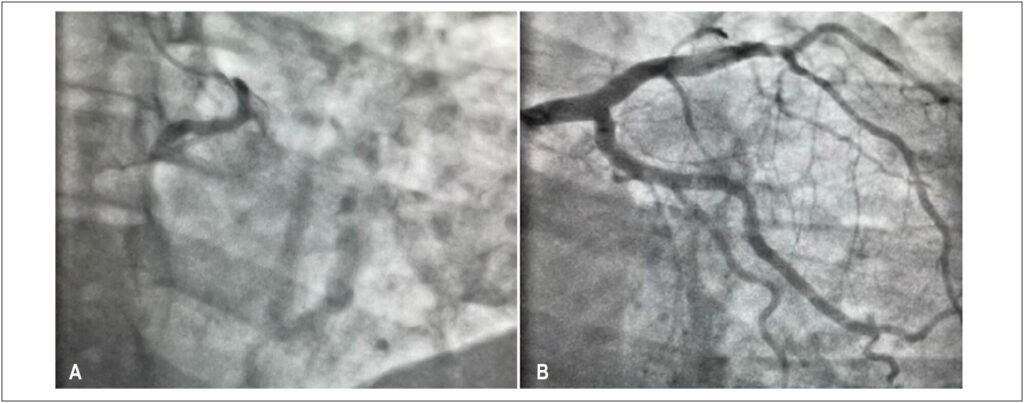

Anomalous Origin of the Right Coronary from the Left Coronary Sinus: How to approach?

Coronary artery anomalies (CAAs) are characterized by a changed vessel origin, path, or structure. It is a rare condition, present in approximately 1% of the general population. These anomalies include the anomalous aortic origin of a coronary artery (AAOCA), which can travel retroaortic, subpulmonic, prepulmonic, and inter-arterial courses.